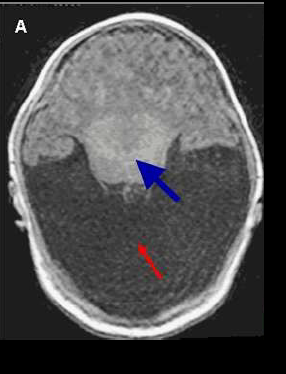

holoprosencefalie

afwijking ten gevolge van neurulatie